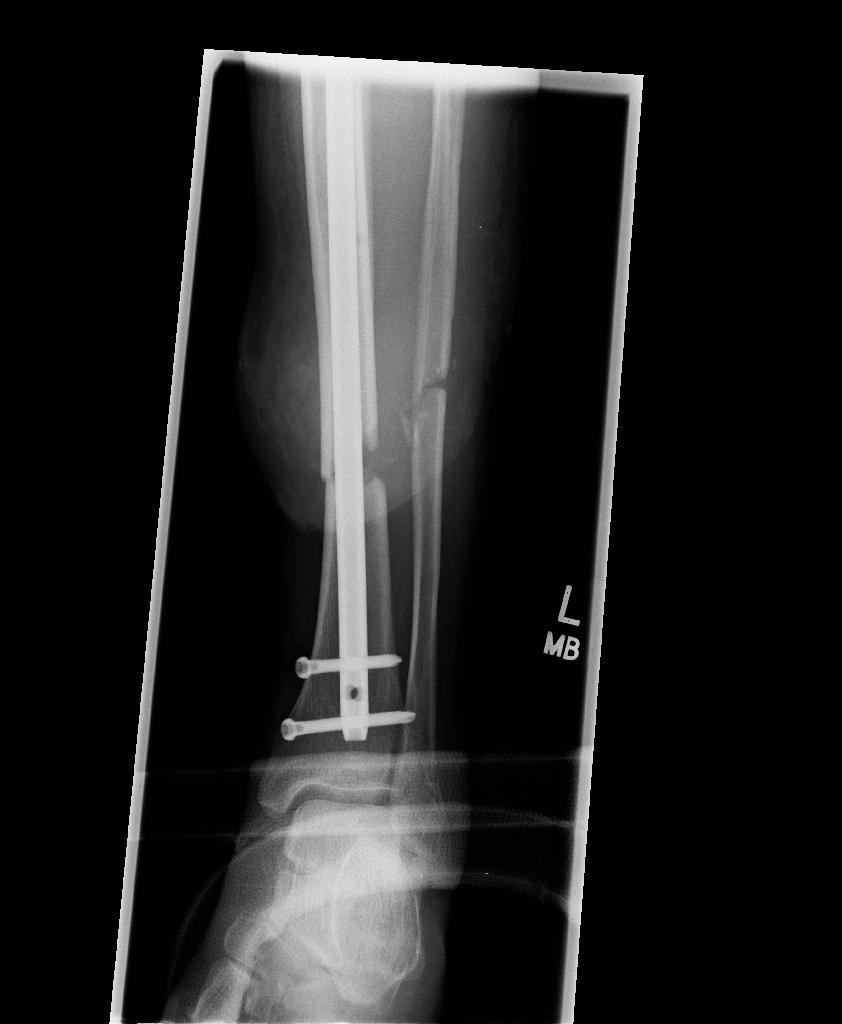

From news reports, Stephen was scooped up onto the hood of an SUV that was barreling down the bridge, flew into the air, thrown into the back end of a bus, and was dumped onto the road, hitting his head, fracturing his skull, neck, back, ribs, puncturing his lung – and shattering bones in his left leg, ripping part of his calf open.

Recovery was long and slow, taking years of physical therapy for Stephen to be able to walk again. He had seven operations on his leg. They had to keep repeating the surgery in order to get the bone to grow properly. A skin flap had to be taken from his right thigh to reconstruct his calf, which was completely ripped open.“The repetition was heartbreaking,” says Stephen. “We’d get our hopes up and then have to go back into surgery over and over again.”